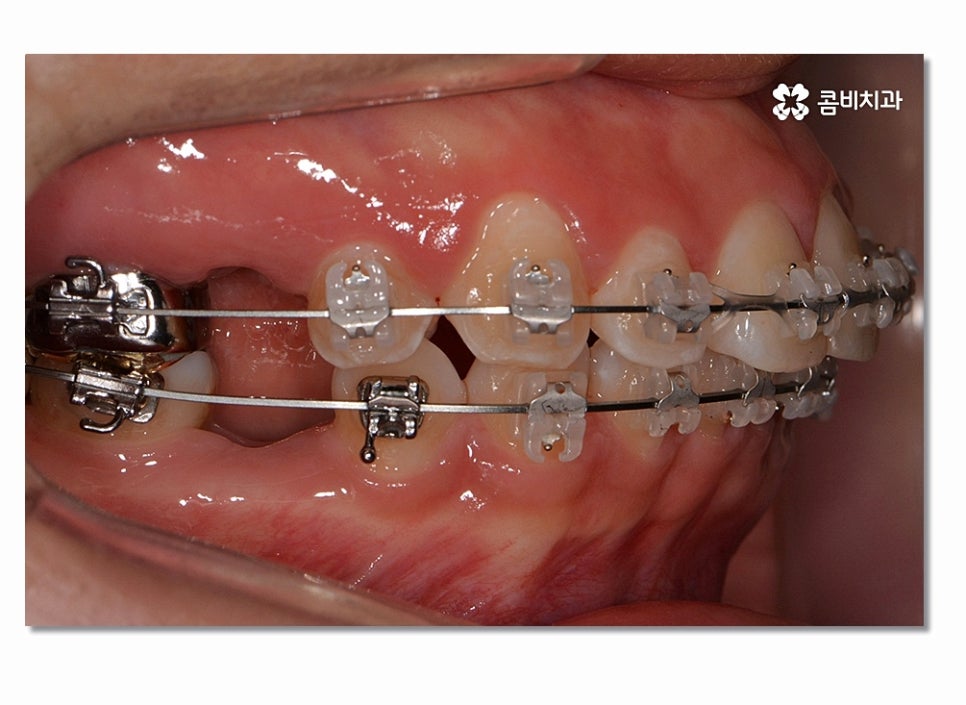

돌출입치아교정이 시작되면 이처럼 전방으로 뻐드러진

앞니를 시간이 지남에 따라서 후방으로 이동시키면서 돌출입이

점점 개선되며 이러한 치열의 변화는 교합도 잘 맞물리도록

위 사진을 보시면 치아교정 과정을 통해서 치열의 가지런함은 물론이며

측면에서 보더라도 돌출입이 많이 개선된 것을 느낄 수 있을 거예요.